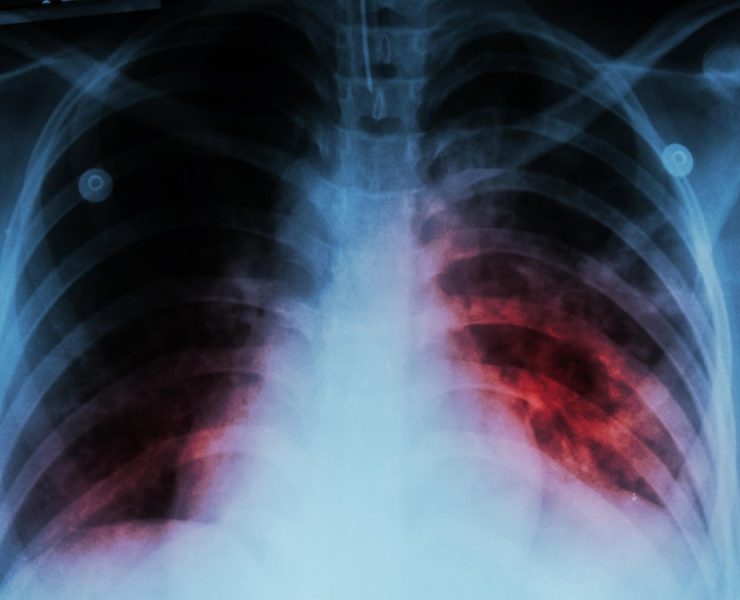

Tuberculosis